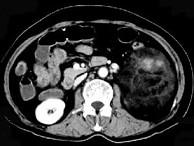

问题 女,64岁,左侧腰部胀痛,行CT扫描,下列说法正确的是 ( )

选项 A、考虑为左侧肾上腺来源的髓样脂肪瘤 B、考虑为腹膜后来源的脂肪肉瘤 C、该病灶密度不均匀,其内可见脂肪密度影,且呈不均匀强化 D、考虑为左肾来源的血管平滑肌脂肪瘤 E、左肾区可见一巨大的占位性病灶,境界较清楚,胰腺尾部受压向前推移

答案 CDE